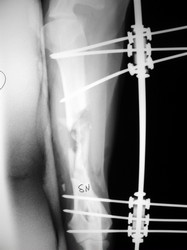

PRÁCTICAS CURSO DE FIJACIÓN EXTERNA PERFECCIONAMIENTO.

Húmero.